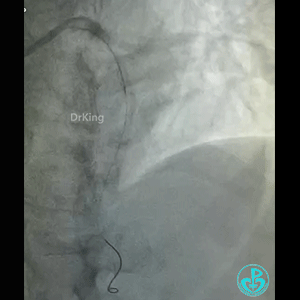

急性前壁心梗,两小时。

导丝怎么扩真怪!急性心梗前降支导丝通过顺利,球囊扩张后导丝移位很多!不在原来的血管腔!_https://www.jmylbn.com_新闻资讯_第1张

导丝怎么扩真怪!急性心梗前降支导丝通过顺利,球囊扩张后导丝移位很多!不在原来的血管腔!